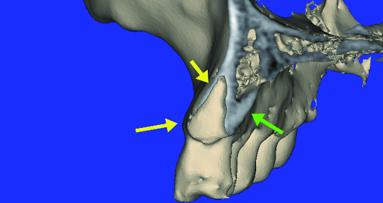

We began by completing the conventional clinical and radiographic examination. Clinically his ridge appeared narrow in the area of tooth #28 and #29, but crestal tissue was keratinised (Figs. 1–3). The patient travelled well over an hour to visit our office and he was aware that we are a proponent of performing flapless guided implant surgery when possible. I explained the benefits and risks associated with this type of implant surgery. The advantages include fast, safe, accurate implant placement with a minimally complicated post-op healing period. Digital 2-D periapical X-rays taken were limited in their diagnostic value. There was no way to be certain as to the exact location of the inferior alveolar nerve or the lingual concavity in the molar area. With that in mind we discussed, and he agreed to accept a CBCT scan to fully evaluate his current condition and determine if enough bone volume existed to perform a guided implant surgery.

This is where my in office CBCT unit becomes invaluable as the information cannot be obtained by any other in office radiographic modality. A medical CT could be requested which exposes the patient to a much larger dose of radiation and could only be taken at a different imaging center. Obviously I could not treat the patient if the existing bone anatomy was deficient and could not accept a properly positioned root form dental implant in solid bone. He was thinking that he could replace four teeth with two implants and a bridge. But that was not appropriate due to the large mesial distal edentulous span of missing teeth. The crest in the area of tooth #29 and #30 exhibited height and labial bone loss. Due to his occlusion, number of missing teeth and the position in the lower right dental arch, I felt it would be necessary to place a minimum of three fixtures to retain a 4-unit fixed bridge.

Sirona’s GALILEOS scan travels around the patients’ head in a single revolution that takes 14 seconds to complete the capture of the maxillofacial anatomy and a full volume of data is reconstructed and becomes available to assess within minutes. My patient and I reviewed the 3-D images together on a large computer monitor in my conference room. I was able to place three virtual implants into the residual bone avoiding the IAN, mental foramen and lingual concavity. Patient could clearly visualise this procedure being performed in his jaw. In this case the bone appeared adequate to receive three endosseous implants that could be restored with a 4-unit fixed bridge (Figs. 4–7). So to recap, this patient was reluctant to be treated with conventional flapped implant surgery and declined additional bone grafting to improve any bone volume, but was a candidate for flapless or minimally flapped guided implant surgery which gave him the confidence to accept treatment based upon our initial consultation and treatment plan which was developed during this visit. This first step is essential to gain the patient’s trust and gain acceptance to the treatment plan at his initial visit as he would not return to us if he wasn’t convinced that I could perform his treatment as I described and under local anesthesia and without further bone grafting.